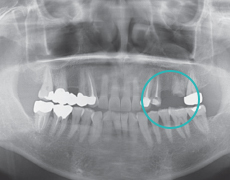

Étape 2

Chirurgie Primaire (plantation de racines artificielles)L'implant est planté dans un endroit approprié.